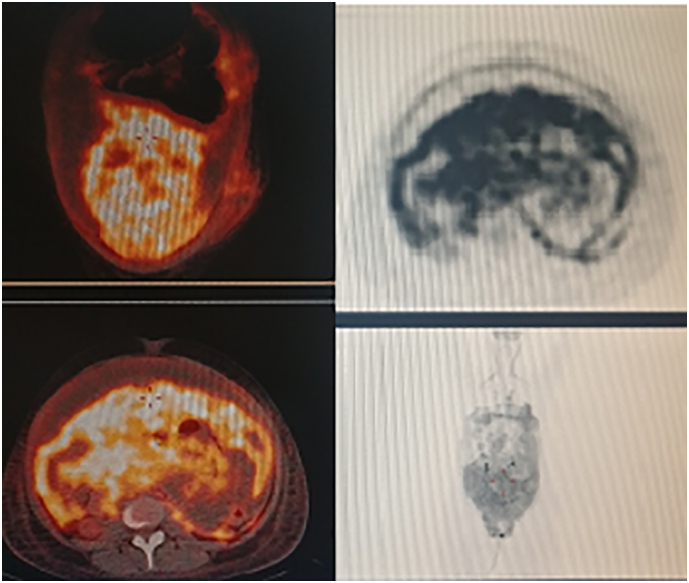

The PET scan revealed increased fluorodeoxyglucose (FDG) uptake in the abdominopelvic regions, consistent with peritoneal carcinomatosis (Fig. 2).

Fig. 2.

PET-FDG confirmed CT-scan findings.